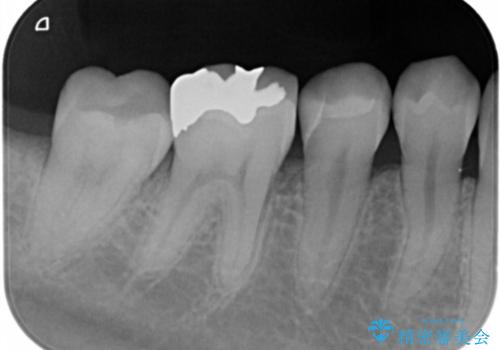

銀の詰め物を外し、拡大鏡で虫歯がないか確認してe-maxインレーで治療をしました。

- e-maxインレー 7.7万円 費用は治療当時の料金となります